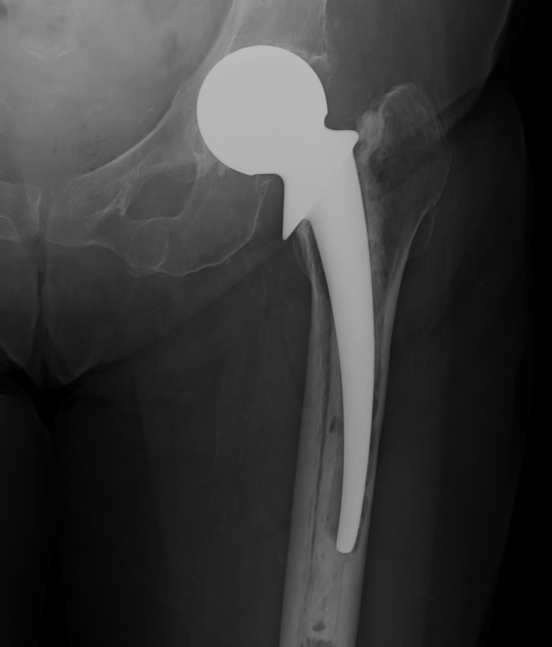

I Minimal metaphyseal cancellous bone loss / intact diaphysis

- i.e. seen after removal of uncemented component without biological ingrowth on surface

II Extensive metaphyseal cancellous bone loss / intact diaphysis

- often seen after removal of cemented prosthesis